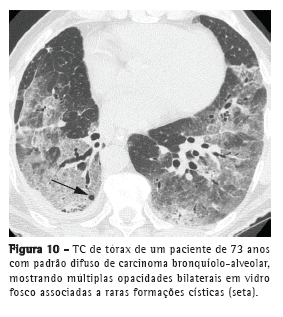

Apresentação difusaO envolvimento difuso do CBA pode representar origem multifocal, disseminação endobrônquica, metástases hematogênicas ou combinações desses padrões. Consolidação, nódulos (Figura 9), opacidades em vidro fosco, broncogramas aéreos e cistos (Figura 10), assim como distribuição periférica e nos lobos inferiores, caracterizam esse padrão.(20) Lesões pulmonares satélites podem ser vistas tanto no CBA, quanto na pneumonia.(18)